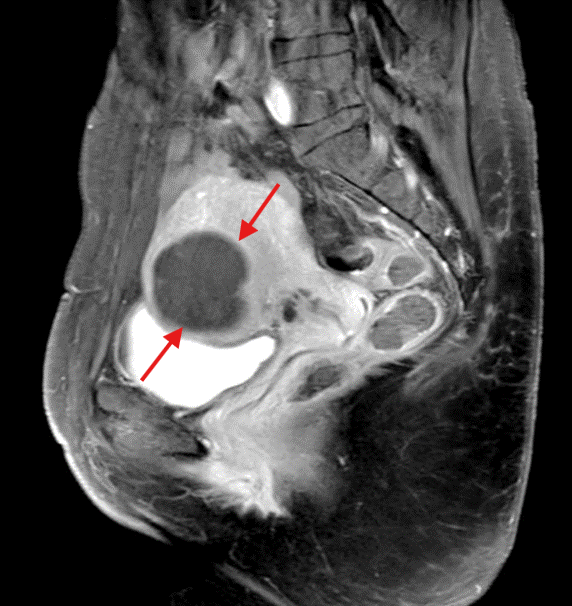

Bertahun lamanya, Sophia (bukan nama sebenar) mengalami haid teruk dan pendarahan banyak yang menyebabkannya tidak bermaya. Lebih membimbangkan, keadaan ini turut menjejaskan emosinya. Di usia 30 tahun, kabinetnya dipenuhi dengan tuala wanita, ubat penahan sakit dan suplemen zat besi, semuanya untuk mengatasi haid yang disangka normal. Namun, Sophia sebenarnya mengalami menorrhagia dan dysmenorrhea, iaitu keadaan yang menyebabkan pendarahan berlebihan dan kesakitan teruk. Kehidupan sehariannya sentiasa bergelut dengan kepayahan, berkejar ke…